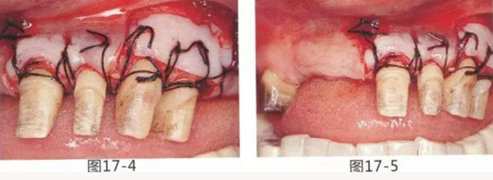

圖17-4 左上1,2進行齦瓣根尖側轉移,左上3,4進行游離牙齦移植,在去除牙周袋的同時獲取附著齦。

圖17-5 牙周治療完成后的正面照。左上3,4部位處游離齦移植片的上端通過骨膜縫合固定在頰側嵴頂部。這樣可以使其愈合效果與齦瓣根尖側轉移相同。